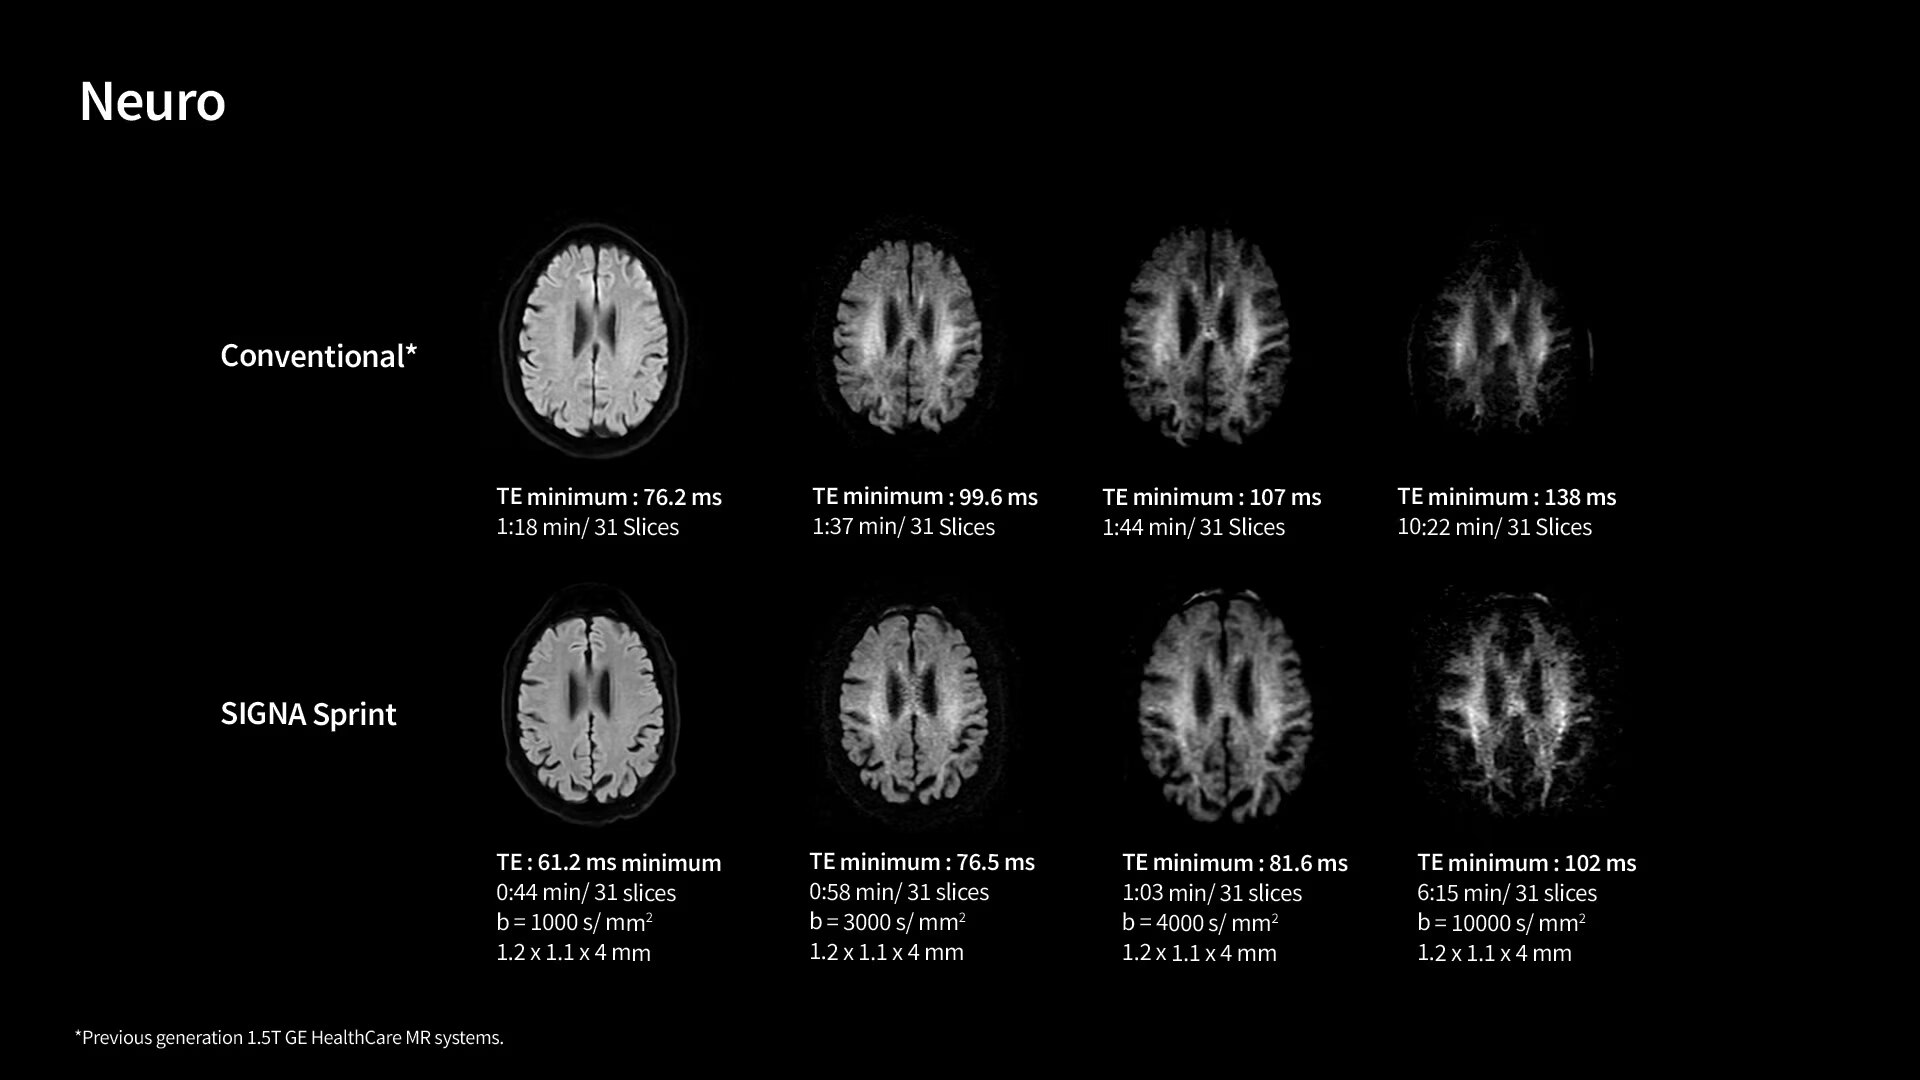

In oncological assessments, diffusion imaging is a critical clinical indicator. SIGNA Sprint offers clearer diffusion, reduced distortion and improved SNR.¹

The growing clinical need within oncology and cardiology requires an MRI scanner that can rise to the challenge. With a high gradient performance of 65/200, SIGNA Sprint helps deliver crystal-clear imaging for ultimate diagnostic confidence. Improved signal-to-noise ratio (SNR) and diffusion, with deep-learning solutions that could enhance diagnostics and treatment response monitoring in your oncology patients.¹ Additionally, the shift from qualitative to quantitative cardiac MRI reduces the time and expertise needed to interpret scans and offers greater consistency and reliability. Helping you to unlock the power to explore further - even in your most challenging cases.